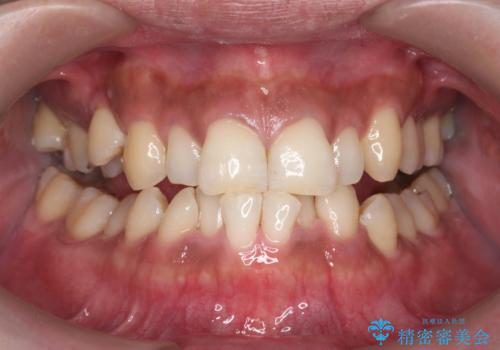

一見きれいに見える歯でも、染め出し(歯垢染色液)を使うとこのように歯と歯茎の境目や、歯と歯の間などに磨き残しがあることがわかります。歯磨きには、いつも気をつけているから磨き残しはナシと思っていても、実際完璧に磨ききることはなかなか難しいです。歯科医院にて、専門の機械で定期的なPMTCを行うことが大切です。